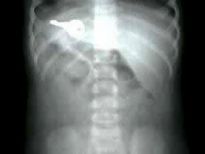

Şoke eden röntgen filmleri

Bu röntgen filmleri görenleri şaşkına çeviriyor!